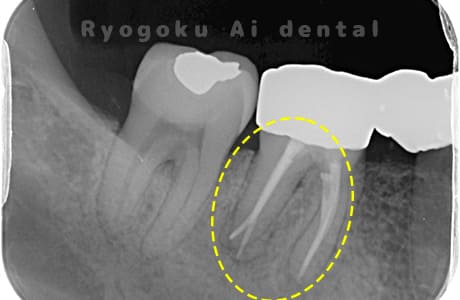

- 原因

- 慢性根尖性歯周炎

- 治療期間

- 3ヶ月

- 治療内容

- マイクロエンド

- 治療費用

- 121,000円

噛むと痛みが出る、とのことで来院した患者様です。他院での根管治療を終えてましたが、根尖病変を認めるため、マイクロエンドを行いました。